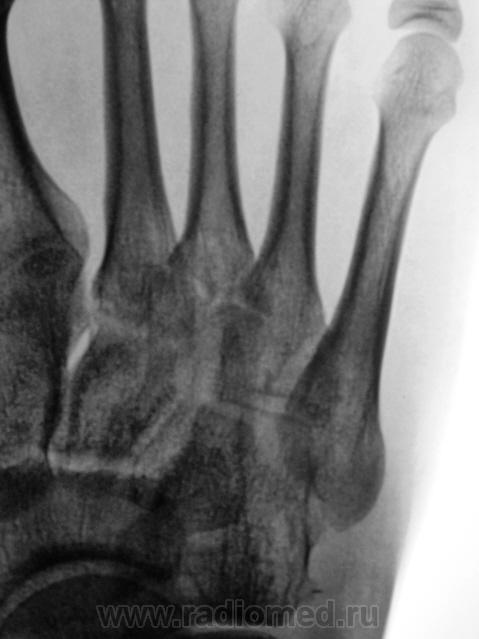

Игорь Иванович, а если взглянуть вот с такого ракурса?

Вы глазастый, и очень уважаемый Виктор Григорьевич!

В десятку попали!

Согласен.

Так а как иначе, чем лоозеровские зоны перестройки.

А. может "стресс-переломом" обругаем...

Оно то конечно можно, дабы поумерить пыл борца на какое то время...по пока, по сути, это не перелом.